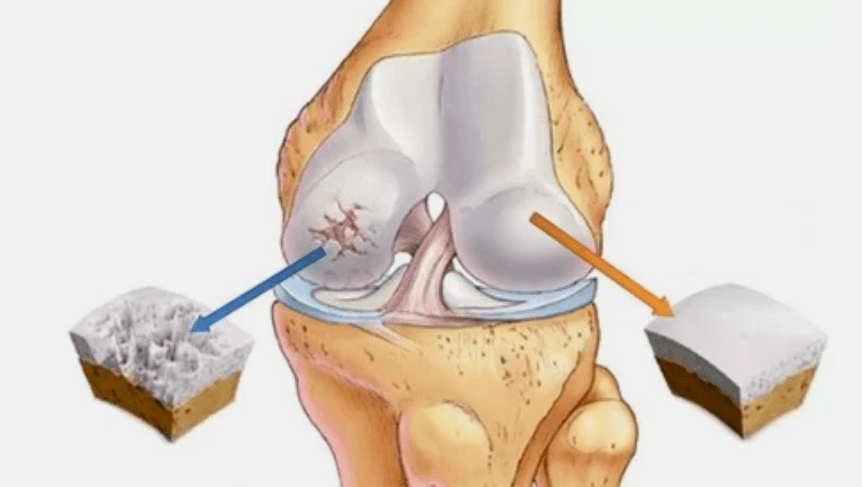

- Hyalin coating pathologies.The slimming of the cartilage leads to the replacement of its pathological tissues: bone structures.

- Anomalous growths appear in the cartilage - osteophytes.

- The violation of the natural anatomy of the cartilage and the bones causes the overload of healthy cartilage areas.The destruction of joint fabrics without treatment constantly progresses and leads to disability.

When the degree of disease increases, pathological processes are still aggravated.In the end, the entire Hyalin cartilage is destroyed.